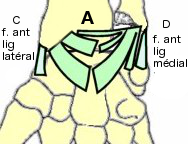

- (A) Le ligament ulno-carpien et radio-carpien palmaire

(old. lig ant.) est

le plus puissant. Il forme 2 faisceaux qui descendent du

radius et du disque articulaire pour converger vers les os du

carpe.

- (B) Le ligament radio-carpien (old.

lig. post.) est formé de 3 faisceaux irradiant du

bord post de l'extrémité inférieure du radius vers le

scaphoïde, le lunatum et le triquétum.

- (C) Le ligament collatéral latéral (old.

lig lat. ext. ou LLE) est formé de 2 faisceaux :

antérieur et postérieur, tendus du processus styloïde du

radius au scaphoïde)

- (D) Le ligament collatéral médial (old.

lig lat. int. ou LLI) est formé de 2 faisceaux

:

- antérieur tendu du processus styloïde de l'ulna au

pisiforme,

- postérieur tendu du processus styloïde de l'ulna au

triquétum (old.

pyramidal).